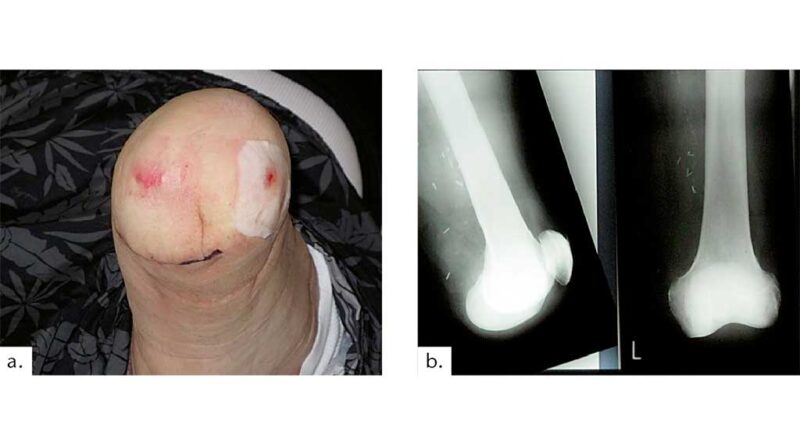

Indikationen für eine Knieexartikulation sind: angeborene Fehlbildungen, periphere arterielle Verschlusskrankheiten, Unfallfolgen, Tumore und Systemerkrankungen. Bei Beugekontrakturen im Knie- und Hüftgelenksbereich ist zunächst eine Knieexartikulation zu versuchen. Bei nicht beherrschbaren Osteomyelitiden im Bereich des Unterschenkels und Fußes mit bereits multiplen rekonstruktiven und Infekt-entfernenden Eingriffen stellt die Knieexartikulation eine ausgesprochen anatomische Wahl der Amputationshöhe dar. Bei mehrfach nachgewiesener aseptischer Lockerung einer Knie-Totalendoprothese sowie multiplen operativen Eingriffen mit Re-Implantationen, die zu erneuten aseptischen Lockerungen und fehlendem „bone stock“ führen, kann ebenso eine Knieexartikulation mit erhaltenem Femurteil der Endoprothese15 indiziert sein.

Druckstellen, die während des Gebrauchs der Knieexartikulationsprothese über der Patella und über dem lateralen und medialen Femurkondylus bei primär korrekter Hautnaht außerhalb der Belastungszone und regelhafter Wundheilung entstehen, zwingen den Amputierten immer wieder, seine gewohnten Aktivitäten des täglichen Lebens einzuschränken (Abb. 11).